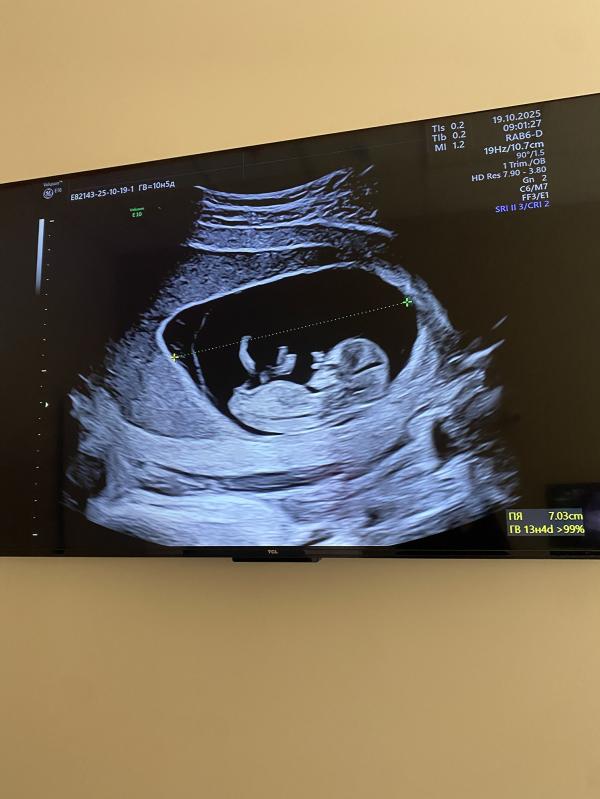

Срок 11,3/5 кто понимает мальчик или девочка ?

Если писька смотрит наверх, то мальчик, если горизонтально-девочка. У вас как-будто мальчик)

Вроде говорят когда бугорок смотри внизу то девочка

Если наверх то мальчик

А вам уже увидели пол? Если нет, то мы тем более не увидим😂 только предположение

Мальчик кажись 🥰